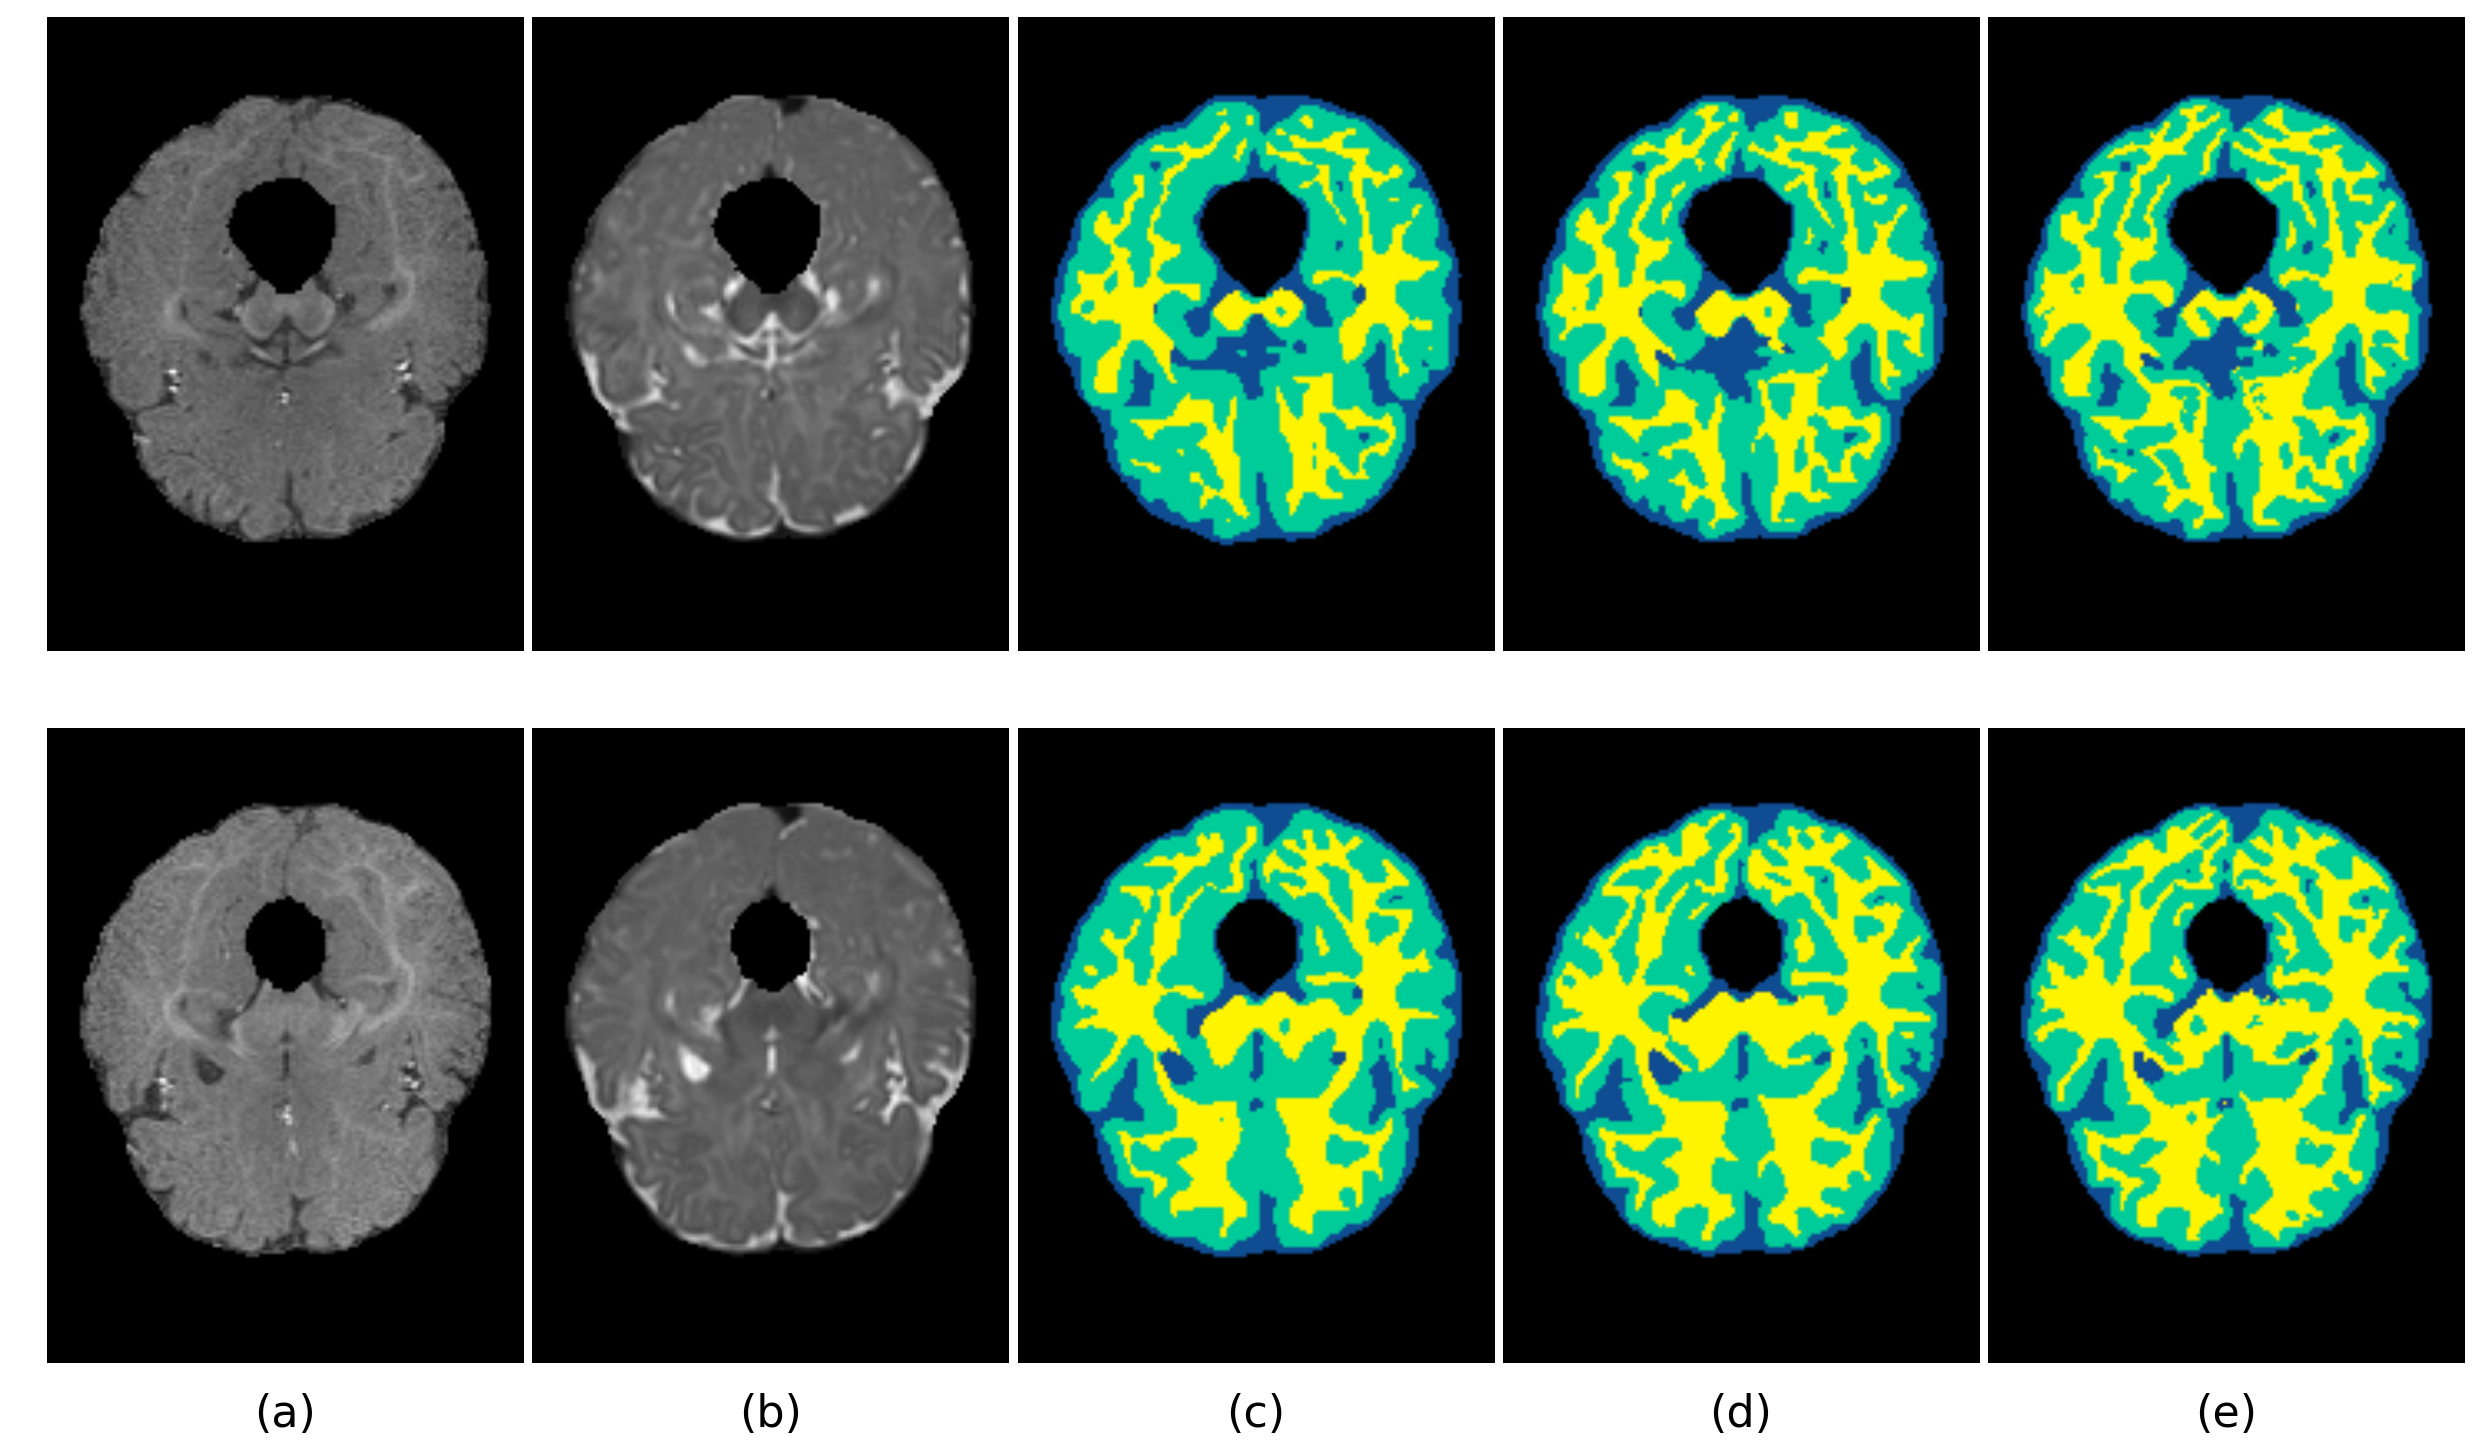

To evaluate the performance of the proposed method, we perform cross-validation on iSeg dataset. Fig. 2 shows the validation results of the proposed method for the ninth subject on different slices. This demonstrates the robustness of the proposed network architecture for accurate segmentation.

Figure 2: Segmentation result on different slice (a) T1 image, (b) T2 image, (c) DenseVoxNet, (d) our result, (e) manual segmentation